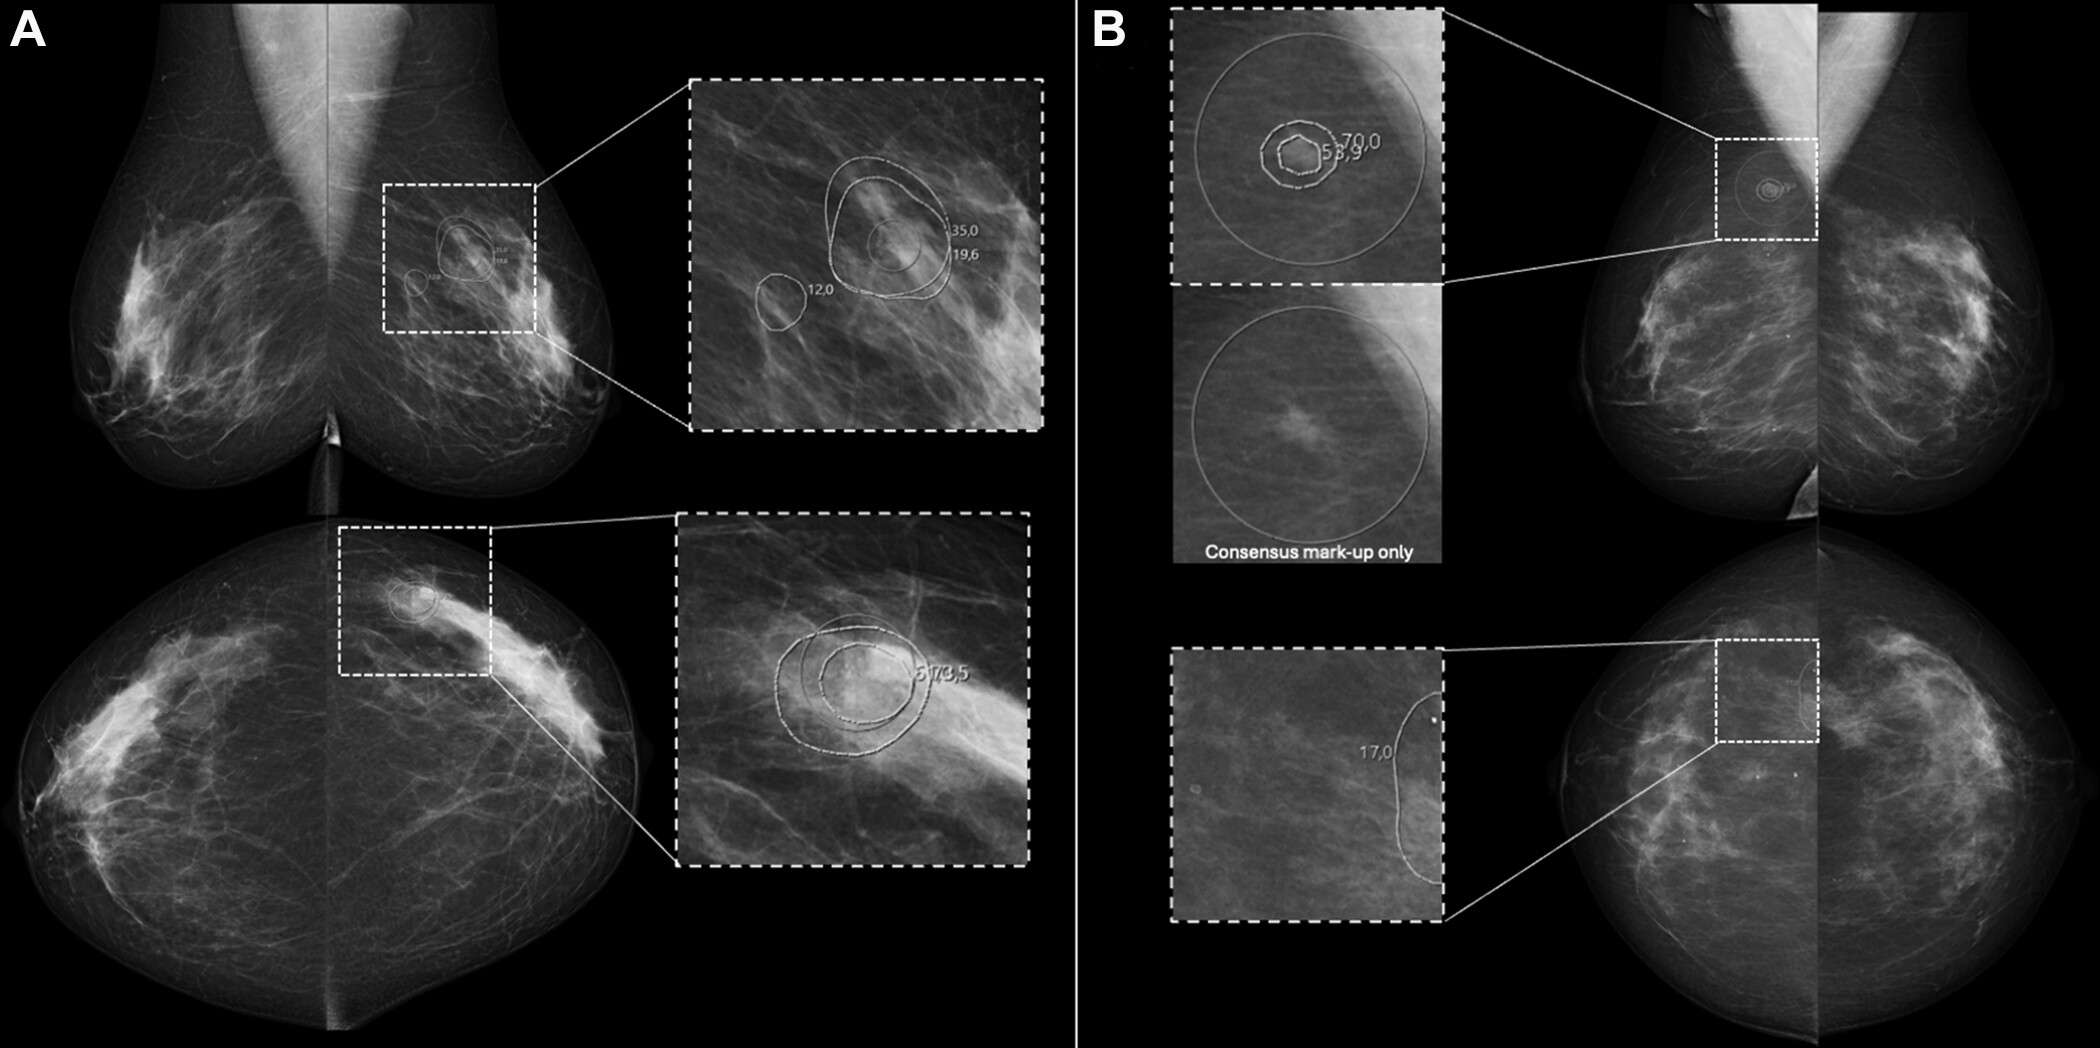

The study covered 215,665 screening mammograms from women, age 40 and over, who received screening mammography between January 1994 and June 1998. Women in the oldest age group (over 70) had a recall rate of 4.9% with a PPV of 12.7%, while those aged 60-69 had a recall rate of 5.8% with a PPV of 8.2%.

The researchers performed regression analyses, which showed that practices with recall rates of 4.4% or less had lower sensitivity than practices that had recall rates of 4.8% or greater. However, the study team did not find a statistically significant increase in sensitivity among the practices after a recall rate of 4.8% was reached.

In addition, a decline in PPV was observed with increasing recall rates for practices with recall rates of 8.9% or greater, and to a lesser extent, for practices with recall rates of 5.9% to 8.7%, according to the researchers.

"Combining these findings, we conclude that practices with recall rates between 4.9% and 5.5% achieve the best trade-off of sensitivity and PPV," they concluded.